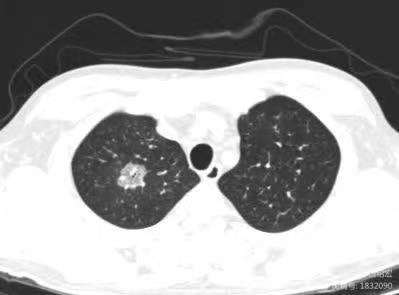

影像上三种表现形式:1. 单纯的血管侵袭可以出现反晕征(如本例),血管截断征、空洞及实变(但本例未出现);2. 单纯的支气管肺侵袭,出现树芽征(主要特征),磨玻璃影及沿支气管的实变;3. 同时有血管、支气管肺侵袭。